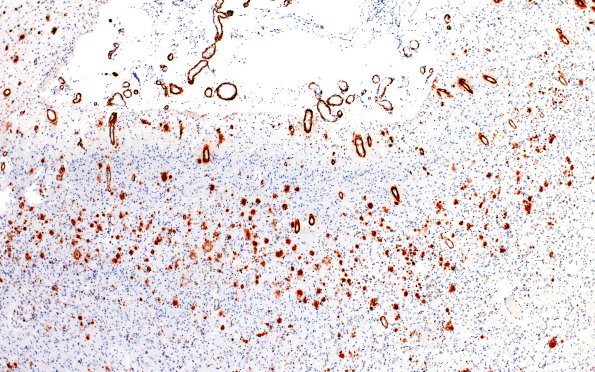

Washington University Experience | NEURODEGENERATION | Pick Disease | 11E2 Pick Dz & ADNC (Case 11) BAmyloid 4X

Amyloid immunoreactivity was variable even within the hippocampus. The amyloid deposition was prominent in the subarachnoid and parenchymal vasculature and within the cerebral cortex. (Beta amyloid, BAP IHC)